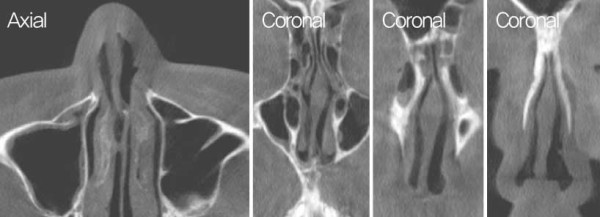

![]()

수술 전 CT 사진. 비중격 상단부의 좌측으로 만곡이 관찰되었다.

수술 전 CT 사진. 비중격 미단부가 우측으로 전위된 모습이 관찰되었다. 좌측

cleft palate 및 nasal spine이 우측으로 전위된 모습과 함께 좌측 상악뼈의

일부 소실이 확인되며, 비중격 미단부 변형 및 비익의 변형으로 인한 우측

비밸브 협착이 관찰되었다.

Cottle test로 우측의 positive가 관찰되었으며, 흡기 시 좌측 비익연골의 허탈이 보였다. 또한 CT 검사에서 좌측 cleft palate가 확인되었으며, 좌측 maxilla 일 부의 결손이 관찰되었고, nasal spine이 우측으로 전 위된 모습이 보였다. 비중격은 상단에서 골부에 걸쳐 좌측으로 high septal deviation이 있었으며, 우측 caudal septum이 우측으로 전위된 것이 확인되었다. 또한 비익연골의 내전과 비중격 미단부 변형으로 인한 우측 비밸브 협착이 관찰되었다.